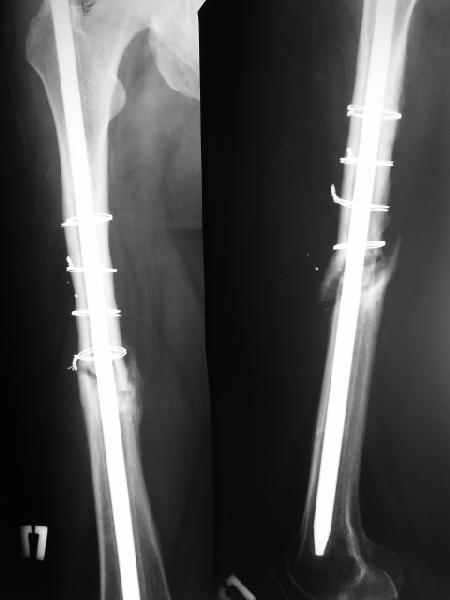

Еще один пример - несращение через полгода после несостоятельного остеосинтеза, и через полгода после реостеосинтеза с блокированием.

1

2